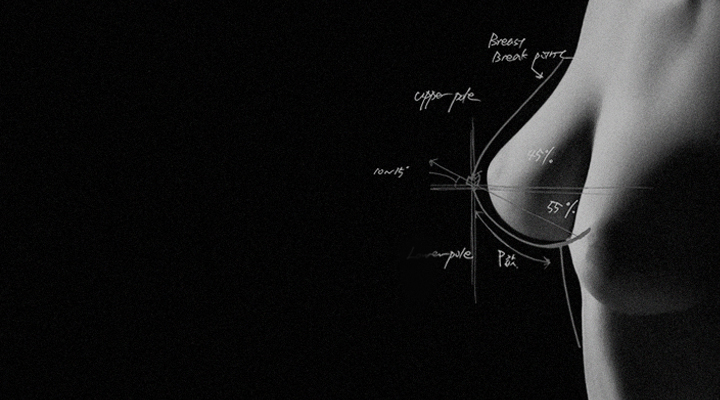

체선율감 시스템으로

1:1 맞춤 수술 집도

나만을 위한 맞춤형 수술 진행!

내 체형에 맞는 [볼륨 라인, 모양, 촉감]을

미리 계획하여 맞춤형 가슴수술 집도합니다.

흉곽에 따른 개별 체형적 특성에 맞춘 가슴수술의

보형물 선택, 수술기법과 그 결과에 대한 고찰

Basic Strategies of Augmentation Mammoplasty in Patients

with Tendencies of Pectus Excavatum and Carinatum (2023)